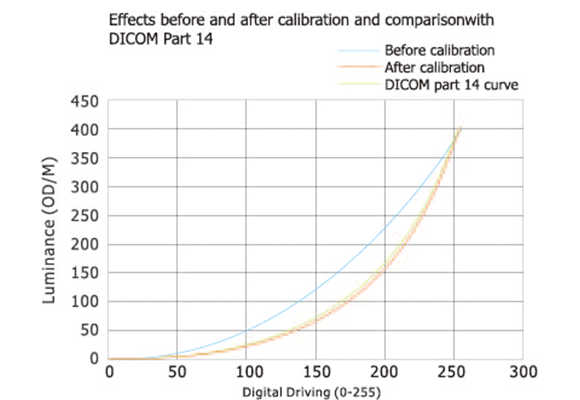

Соответствие Стандарту DICOM

Медицинские изображения, включая самые тонкие детали, могут отображаться точно. Сохранить последовательность отображения между различными дисплеями, а также отображения и различных форм изображения, обеспечить точность диагностики.

Система Стабилизации Заднего Освещения

Встроенный встроенный датчик подсветки постоянно контролирует яркость подсветки. Он может быстро достичь стабильности яркости при запуске и автоматически компенсировать изменения температуры окружающей среды и потери яркости, вызванные длительным использованием, сохраняя последовательность яркости на протяжении всего жизненного цикла продукта.